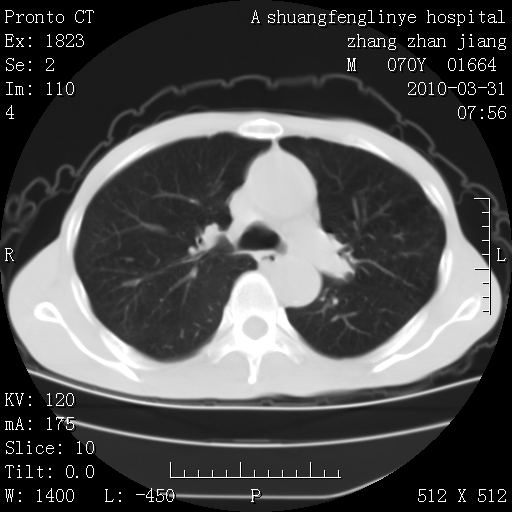

标题: CT25450:肺结核?

双上肺继发型tb并左上空洞形成,主动脉冠脉钙化。

支持:继发性肺结核伴空洞形成!建议纤支镜检查待出外周围型肺癌可能!

1)两肺上叶继发性肺结核并左肺上叶空洞形成。2)冠状动脉及主动脉钙化。